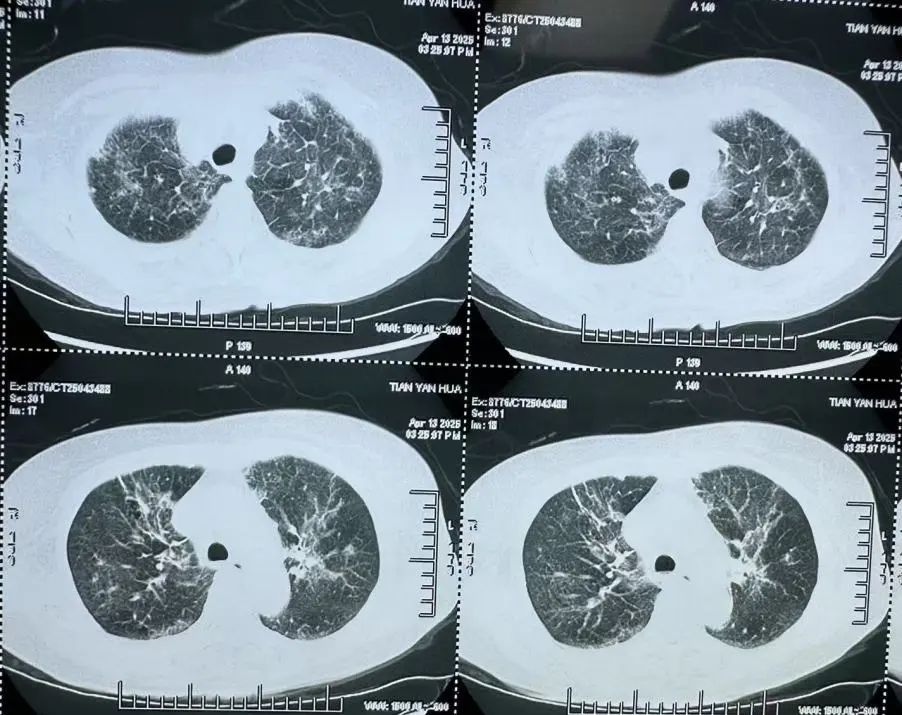

非HIV-PCP肺部影像

非HIV-PCP的早期症状与普通肺炎相似,但进展更快,48小时内可能引发呼吸衰竭。有免疫缺陷病史(如肿瘤化疗、器官移植、风湿免疫病长期用药)等高危人群一旦出现持续发热>1周,抗生素治疗无效;干咳、进行性呼吸困难;血氧饱和度<93%等症状应立即到呼吸与危重症医学科就医,进行支气管镜肺泡灌洗检查。